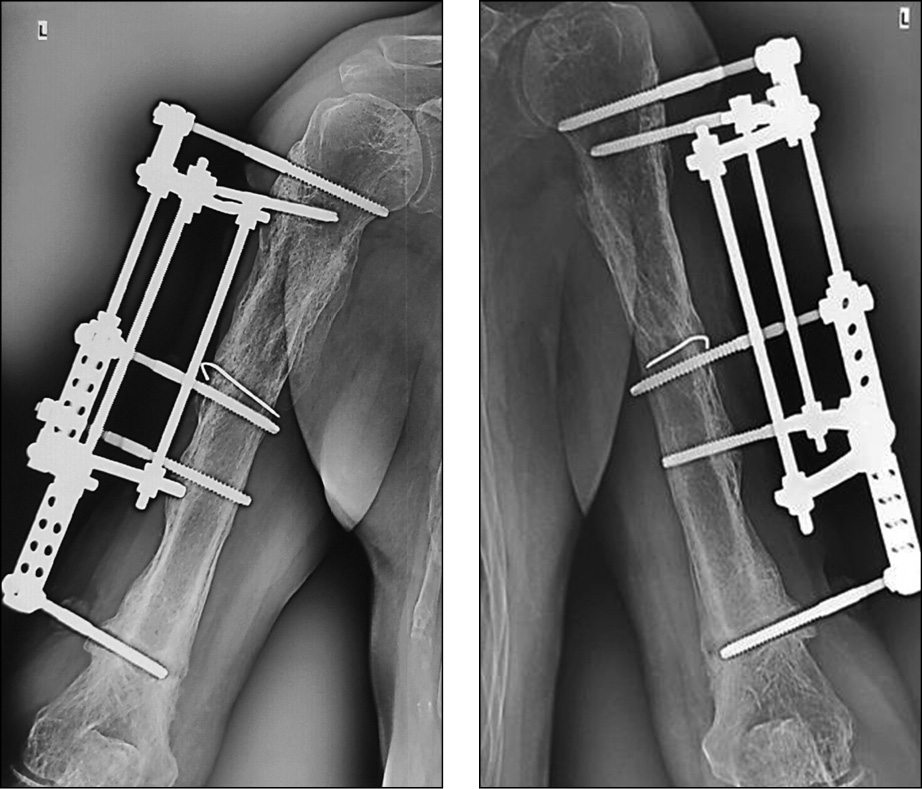

В условиях нашей клиники выполнена операция: 1. Экономная резекционная секвестрнекрэктомия левой плечевой кости. 2. Реостеосинтез левой плечевой кости аппаратом внешней фиксации стержневой компоновки (рис. 7).

Рис. 7. Рентгенограммы левой плечевой кости после операции

Резекция костной ткани осуществлена в пределах жизнеспособной ткани. Согласно критериям биомеханической концепции, двухрычаговый перелом зафиксирован на 4 уровнях фиксации, по 2 уровня на каждом отломке. Рана была дренирована. В послеоперационном периоде проведена антибактериальная терапия [с учетом данных микробиологического исследования — метициллинрезистентный золотистый стафилококк (MRSA)]: Ванкомицин по 1 г 2 раза в день в/в капельно 12 дней. Параллельно проводили противовоспалительную, инфузионную терапию. Послеоперационная рана зажила первичным натяжением. Дренажная трубка удалена на третьи сутки.